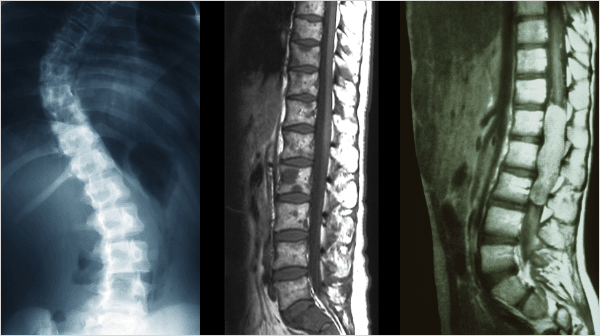

척추측만증,후만증,전만증

추의 만곡이 소실되어 척추가 왼쪽 혹은 오른쪽으로 휘어지는 증상을 척추측만증,

허리뼈가 아무런 굴곡없이 일자로 꼿꼿한 허리를 후만증, 앞쪽으로 휘어지는 증상을 전만증 이라고 합니다.

정상

비정상